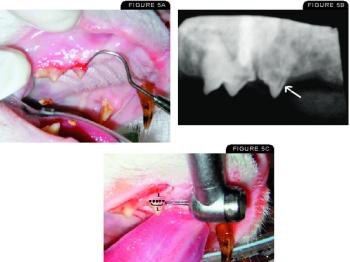

In May, I explained how to perform a nonsurgical extraction on single-rooted teeth including the incisors, first premolars, deciduous canines, and mandibular third molars. A surgical approach is indicated to extract canines, certain large incisors, and multirooted teeth and to retrieve root tips.